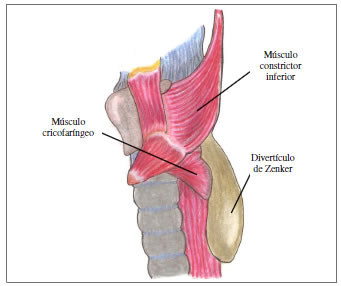

Los divertículos falsos se pueden formar por dos mecanismos. el primero por impulsión: existe un aumento de la presión intraluminal que ocasiona protrusión de la mucosa a través de un defecto de la pared, como es el caso del divertículo de Zenker (figura 1); el segundo es por tracción: existe una presión externa que forma los divertículos 2.

Figura 1. Ilustración anatómica del divertículo de Zenker.

El divertículo de Zenker es un divertículo falso por impulsión que fue descrito por primera vez por Abraham Ludlow en 1764 3. Sin embargo, no fue sino hasta 1878 cuando los patólogos alemanes Friedrich Albert von Zenker y Hugo von Ziemssen describieron 23 casos del divertículo que después llevaría el nombre de Zenker 4. Su fisiopatología no es clara. La hipótesis más aceptada es el aumento de la presión intraluminal secundaria a la incoordinación motora del esfínter esofágico superior, que facilita la herniación de la mucosa esofágica a través del triángulo de Killian y la aparición del divertículo de Zenker. Dicha incoordinación motora se asocia con la edad avanzada 2,5.